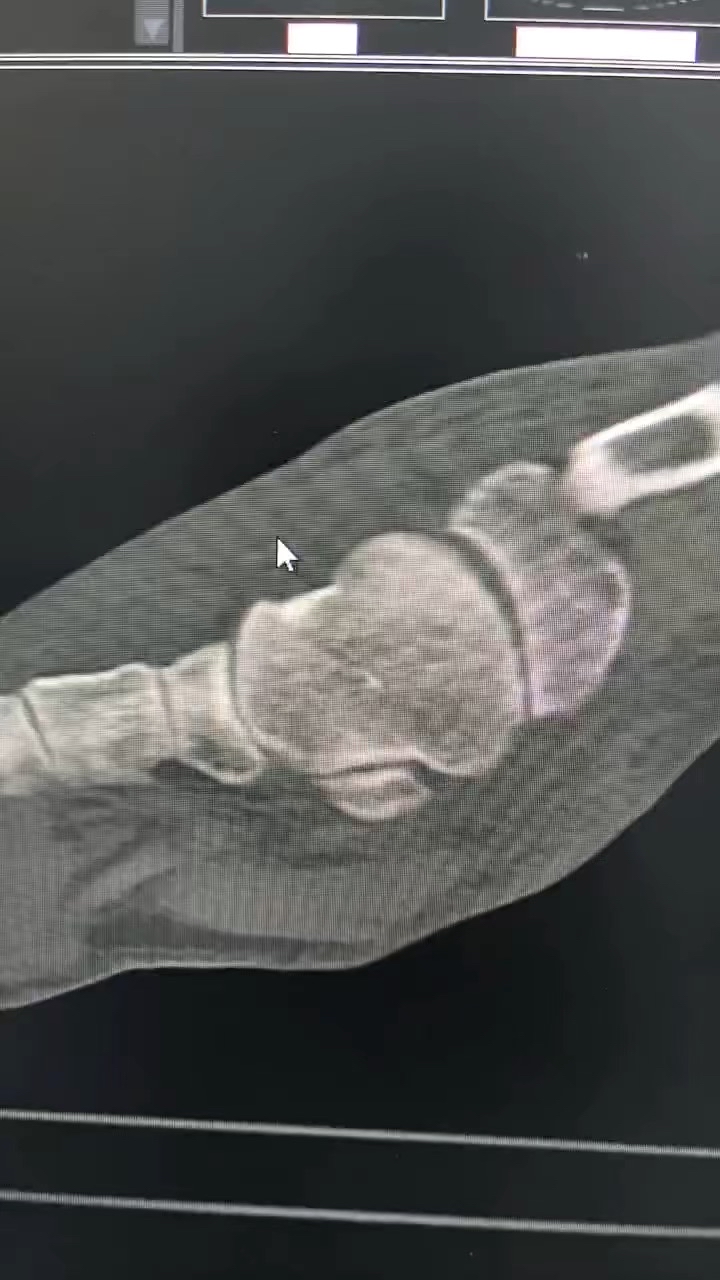

病例跟骨骨折(sanders IV)微创手术

【患者信息】:男性

【主诉】:外伤致左足疼痛10天

【现病史及既往史】:糖尿病

【检查】:外院跟骨骨折

【临床诊断】:跟骨骨折

【治疗经过及结果】:入院后行手术治疗